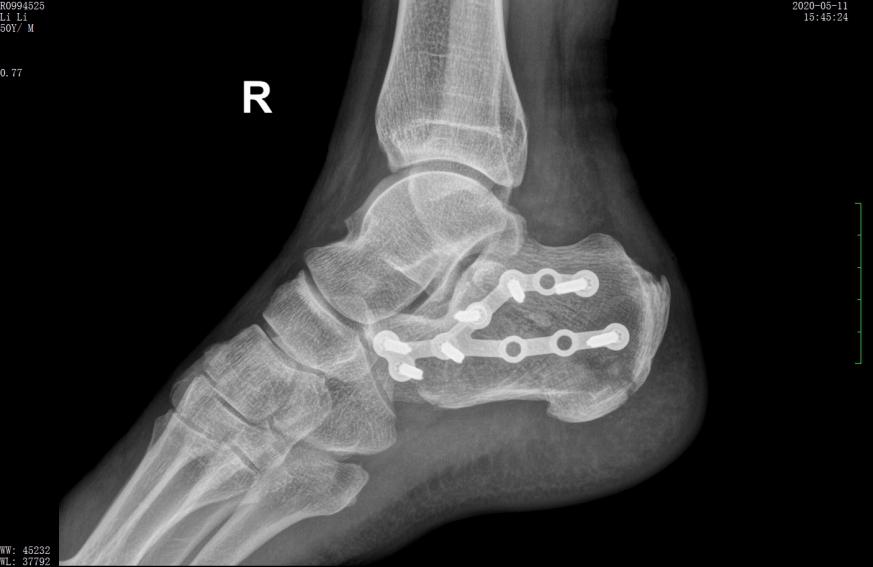

行微创手术治疗后,跟骨高度恢复,关节面平整

术后X线示骨折复位良好